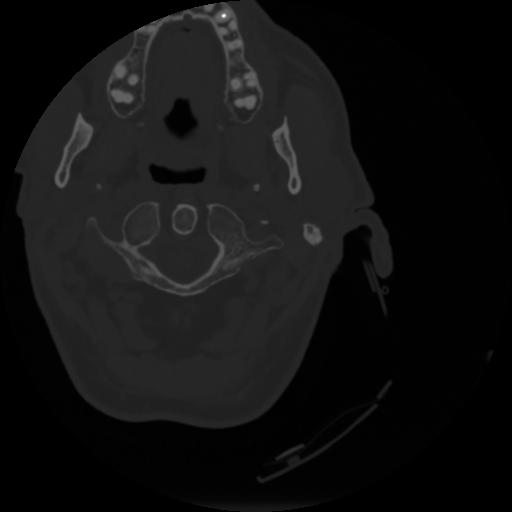

4 CEREBRO,,Vol,0.5,CEREBRO,,